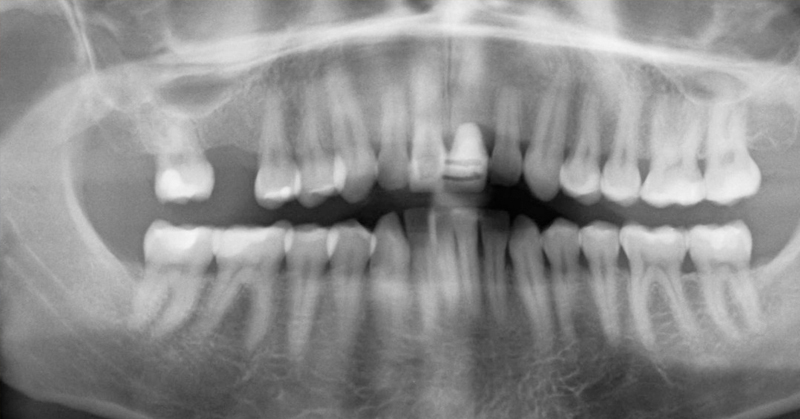

Old  Default Hãy cẩn thận: Khoang miệng có thể giết chết bạn!?!

Bạn có biết những gì thực sự đang xảy ra trong miệng của bạn?

Hiện nay, ngày càng có nhiều người đang tìm đến nha sĩ để giúp điều trị các vấn đề về răng như là một kết quả của một chế độ ăn uống và lối sống thiếu khoa học. Sự kết hợp không lành mạnh này chuyển thành một số điều kiện khác nhau mà có thể có ảnh hưởng lâu dài đến sức khỏe tổng thể của bạn.

Phần đáng sợ là không có nhiều người nhận thức được làm thế nào những vấn đề này có thể tác động tới sức khỏe của mình. Ví dụ, bạn có biết rằng các bệnh tự miễn dịch, rối loạn thần kinh, cũng như các bệnh mãn tính và cấp tính có thể xảy ra do ngộ độc thủy ngân trong trám amalgam?

Đồng thời, có những vấn đề khác có thể phát sinh từ nhiễm trùng mà đến như là một kết quả của ống tủy hoặc nhổ răng - về cơ bản, một khi bạn đi đến nha sĩ, điều đó không nhất thiết có nghĩa là nó là kết thúc của câu chuyện.

Răng của bạn là cơ quan riêng biệt.

Mỗi răng của bạn được liên kết với các cơ quan khác, các tuyến, và các mô mà biến cơ thể của bạn thành một mạng lưới các hệ thống hoạt động. Vì vậy, khi bạn đối phó với những vấn đề bên trong miệng của bạn, họ có thể lây lan đến các bộ phận khác của cơ thể của bạn nhanh chóng. Điều này có thể có một tác động có hại đến sức khỏe của hệ thống miễn dịch của bạn, và kết quả là một cơn lũ độc tố góp phần vào sự suy thoái của các mô và cơ quan của bạn.

Đâu là giải pháp cho bạn?

Trong khi các vấn đề của răng đã rất nghiêm trọng, những vấn đề về răng có thể lây lan và tiếp tục lây nhiễm sang các bộ phận khác của cơ thể của bạn nhanh chóng. Đó là lý do tại sao điều quan trọng là phải chăm sóc chúng trong những cách lành mạnh nhất và nhanh nhất có thể, để giảm thiểu thiệt hại và đảm bảo rằng miệng của bạn vẫn khỏe mạnh trong một thời gian dài.